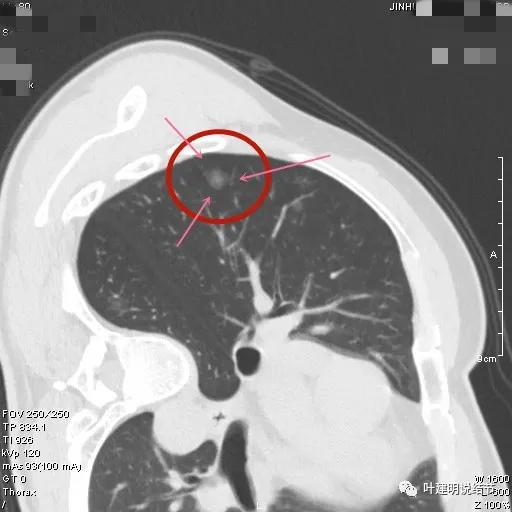

病灶密度较低,膨胀性略,瘤肺边界在靶扫描上还是显得有些清晰的

病灶瘤肺边界清,密度偏低,有点散,但有微小血管进入(桔色箭头)

病灶整体密度较低,但轮廓较清,内部密度不大均匀,显得杂乱

不均质的偏低密度磨玻璃结节,轮廓清